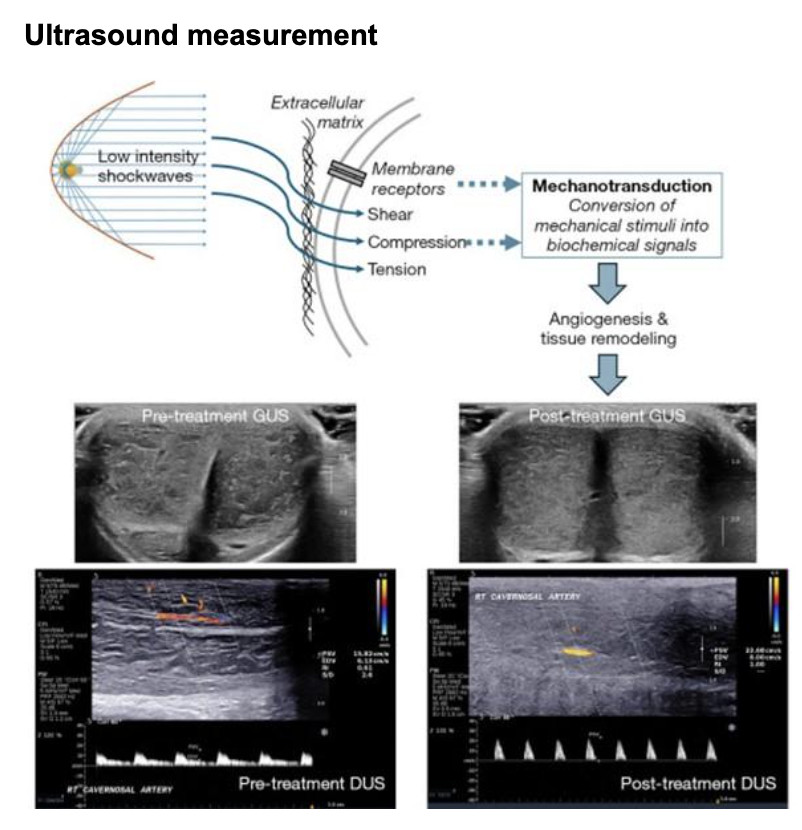

The novel study published in October 2024 by Sue Goldstein, Dr. Irwin Goldstein, and Dr. Noel Kim from the University of San Diego, California, investigated the improvement on erectile tissue quality following Spark Wave application, validating the hypothesis of the multiple beneficial improvements within the penile tissue, and including a novel observation on erectile tissue homogeneity.

The observational study published in July 2024, by Mateo Rubino and colleagues, with the participation of Prof. Carlo Bettocchi from the University of Foggia, Italy; similarly demonstrated an increase in blood flow velocity and improvement in erectile quality in non-diabetic patients. The therapy appears particularly beneficial for patients with mild to moderate vascular erectile dysfunction. Both studies demonstrate that shockwave therapy is a safe, effective, and proven regenerative treatment option in urology.

- Significantly improves erectile function (IIEF)

- Significantly more patients reached an erection that lasted long enough for successful intercourse Objective greyscale ultrasound measurement correlates with erectile function score

- Increases blood pressure in the penis

- Most effective for moderate ED